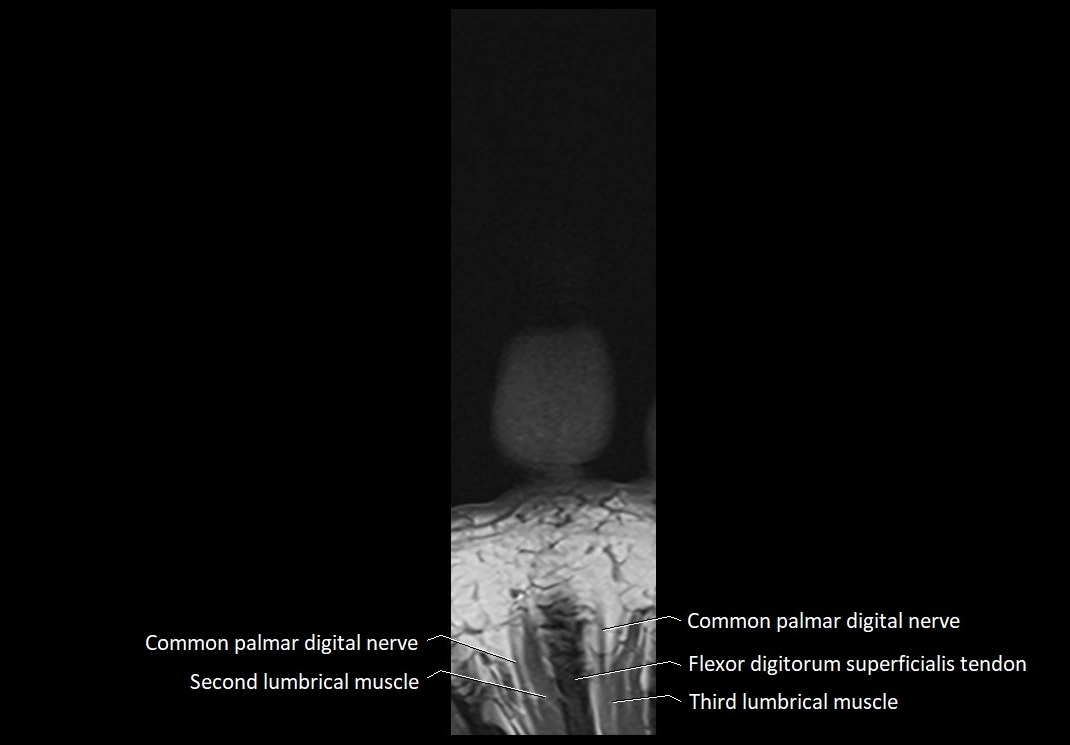

MRI image